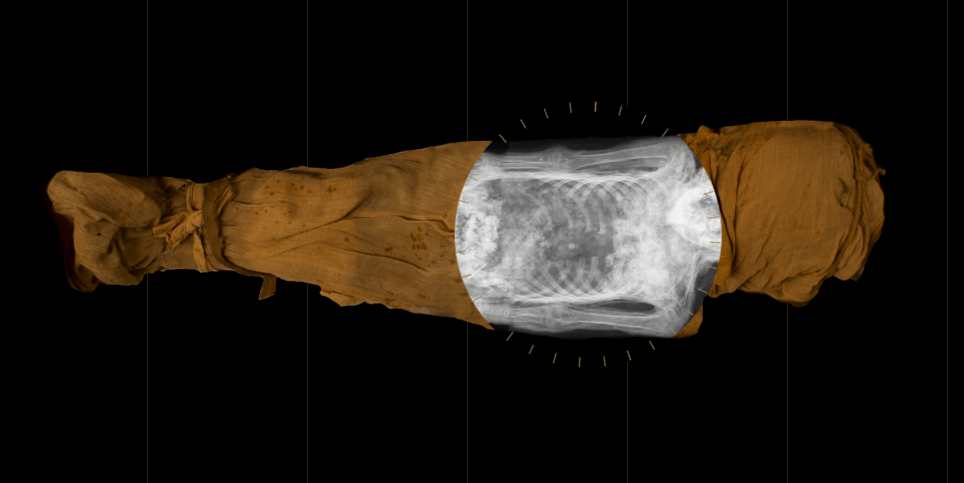

Image of the mysterious lady of the National Museum in WarsawWarsaw Mummy Project

Since the 1920s, researchers in Poland were under the impression that an ancient Egyptian mummy they were housing was a male priest named Hor-Djehuty. But a recent radiological analysis revealed an anomaly near the pelvis of the entombed: a tiny foot.

But computer tomography conducted in 2016 suggested the mummy might be female, revealing a delicate bone structure, long hair, and mummified breasts.